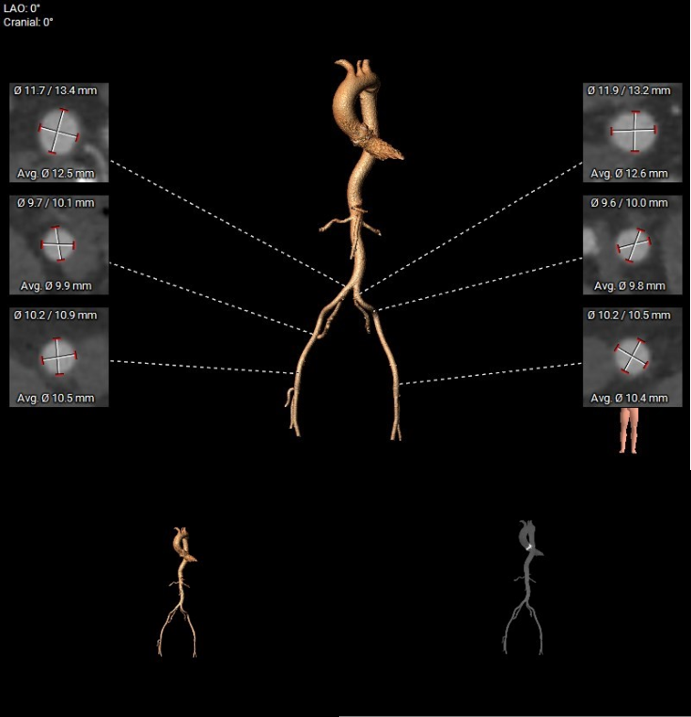

4.双侧股动脉入路血管管径良好。

外周血管及主动脉弓解剖:

3.患者双侧入路血管条件佳,常规选择右侧股动脉为主入路,左侧为辅入路。